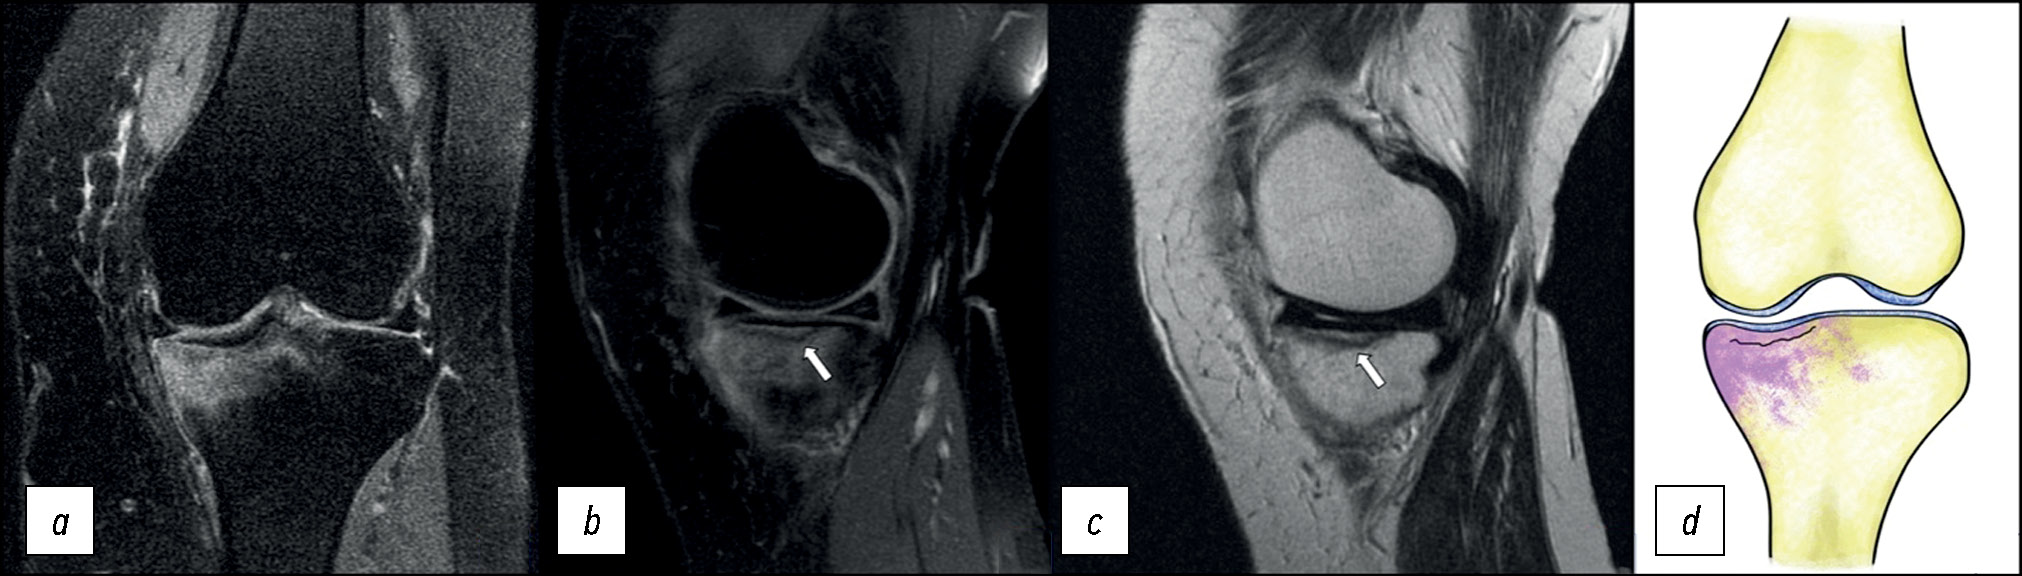

Из особенностей МРТ-картины отмечается невыраженный отёк в субхондральной зоне внутреннего мыщелка бедренной кости с наличием гипоинтенсивной линии, отделяющей фрагмент гиалинового хряща и костной ткани (рис. 5).

Рис. 5. МР-томограммы коленного сустава: a, b — корональная и сагиттальная проекции в режиме PD с подавлением сигнала от жировой ткани при рассекающем остеохондрите внутреннего мыщелка правой бедренной кости; с — графическое изображение.

Fig. 5. MRI scans of the knee: a, b — coronal and sagittal views in to suppress the signal from adipose tissue with an osteochondritis dissecans (OCD) medial condyle of the femur. Graphic image (с).

Выявленные изменения стали основанием для диагноза «рассекающий остеохондрит внутреннего мыщелка бедренной кости справа».

Интенсивность отёка в данном случае зависит от активности и срока возникновения повреждения. При длительном вялотекущем процессе интенсивность отёка, как правило, снижается.

Данные изменения можно выявить на рентгенограммах в виде овального поражения субхондральной кости с различной степенью прозрачности в центре и окружающим склерозом. Данное заболевание характерно для пациентов подросткового или молодого возраста, активно занимающихся спортом.